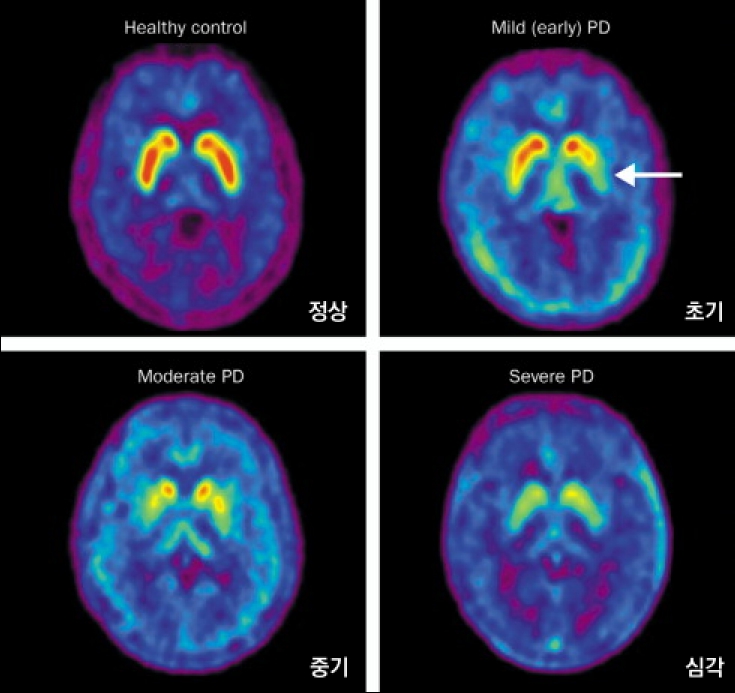

방사성의약품 전문 기업 듀켐바이오(대표 김종우)의 뇌질환 진단제 ‘에프도파18F (제품명 도파체크주사)’가 파킨슨 진단 시에도 쓰이게 됐다.

20일 듀켐바이오에 따르면 도파체크주사는 뇌종양, 신경내분비종양, 갈색세포종 진단을 위해 사용해온 방사성의약품이다. PET-CT 촬영 시 함께 쓰인다.

김종우 듀켐바이오 대표는 “뇌질환은 부위 특성상 조직검사가 어려워 방사성의약품을 통한 진단 확대가 더욱 필요하다”며 “FP-CIT와 도파체크주사가 상호 보완 역할을 하면서 파킨슨 질환 조기 진단에 힘을 보탤 것”이라고 말했다.